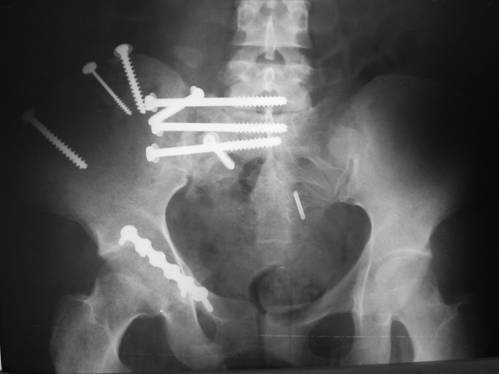

23.09.2003. Одновременный остеосинтез переднего и заднего тазовых полуколец

Результат через 10 дней